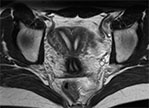

Пример МРТ матки

МРТ матки

На серии МР томограмм взвешенных по Т1 и Т2 с жироподавлением в трёх проекциях:

Вход в малый таз имеет овальную форму, крылья подвздошных костей и мышцы развиты правильно. Матка обычного расположения (anteversio anteflexio) с четкими, ровными контурами.

В полости матки продольная гипоинтенсивная перегородка на широком основании, достигающая наружного зева цервикального канала, прерывающаяся на уровне перешейка матки на протяжении до 14мм, о распространении перегородки на верхние отделы влагалища достоверно судить не представляется возможным. В области дна матки определяется щель глубиной не более 1,5мм

В Дугласовом пространстве определяется умеренное количество свободной жидкости.

Эндометрий хорошо дифференцируется, без патологических включений.

Прямая кишка без видимых изменений, утолщения стенок и наличие новообразований не выявлено. Параректальная клетчатка не инфильтрирована.

Мочевой пузырь равномерно заполнен, содержимое его однородное и соответствует жидкости. Стенки мочевого пузыря не утолщены. Паравезикальное пространство - без особенностей.

Клетчаточные пространства таза дифференцированы. Крупные сосуды таза не изменены. Увеличенных лимфоузлов, костной деструкции на исследованном уровне не определяется.

ЗАКЛЮЧЕНИЕ по снимку МРТ матки: МР-признаки вероятнее всего соответствуют полной перегородке матки (5 группа аномалий развития мюллеровых протоков).